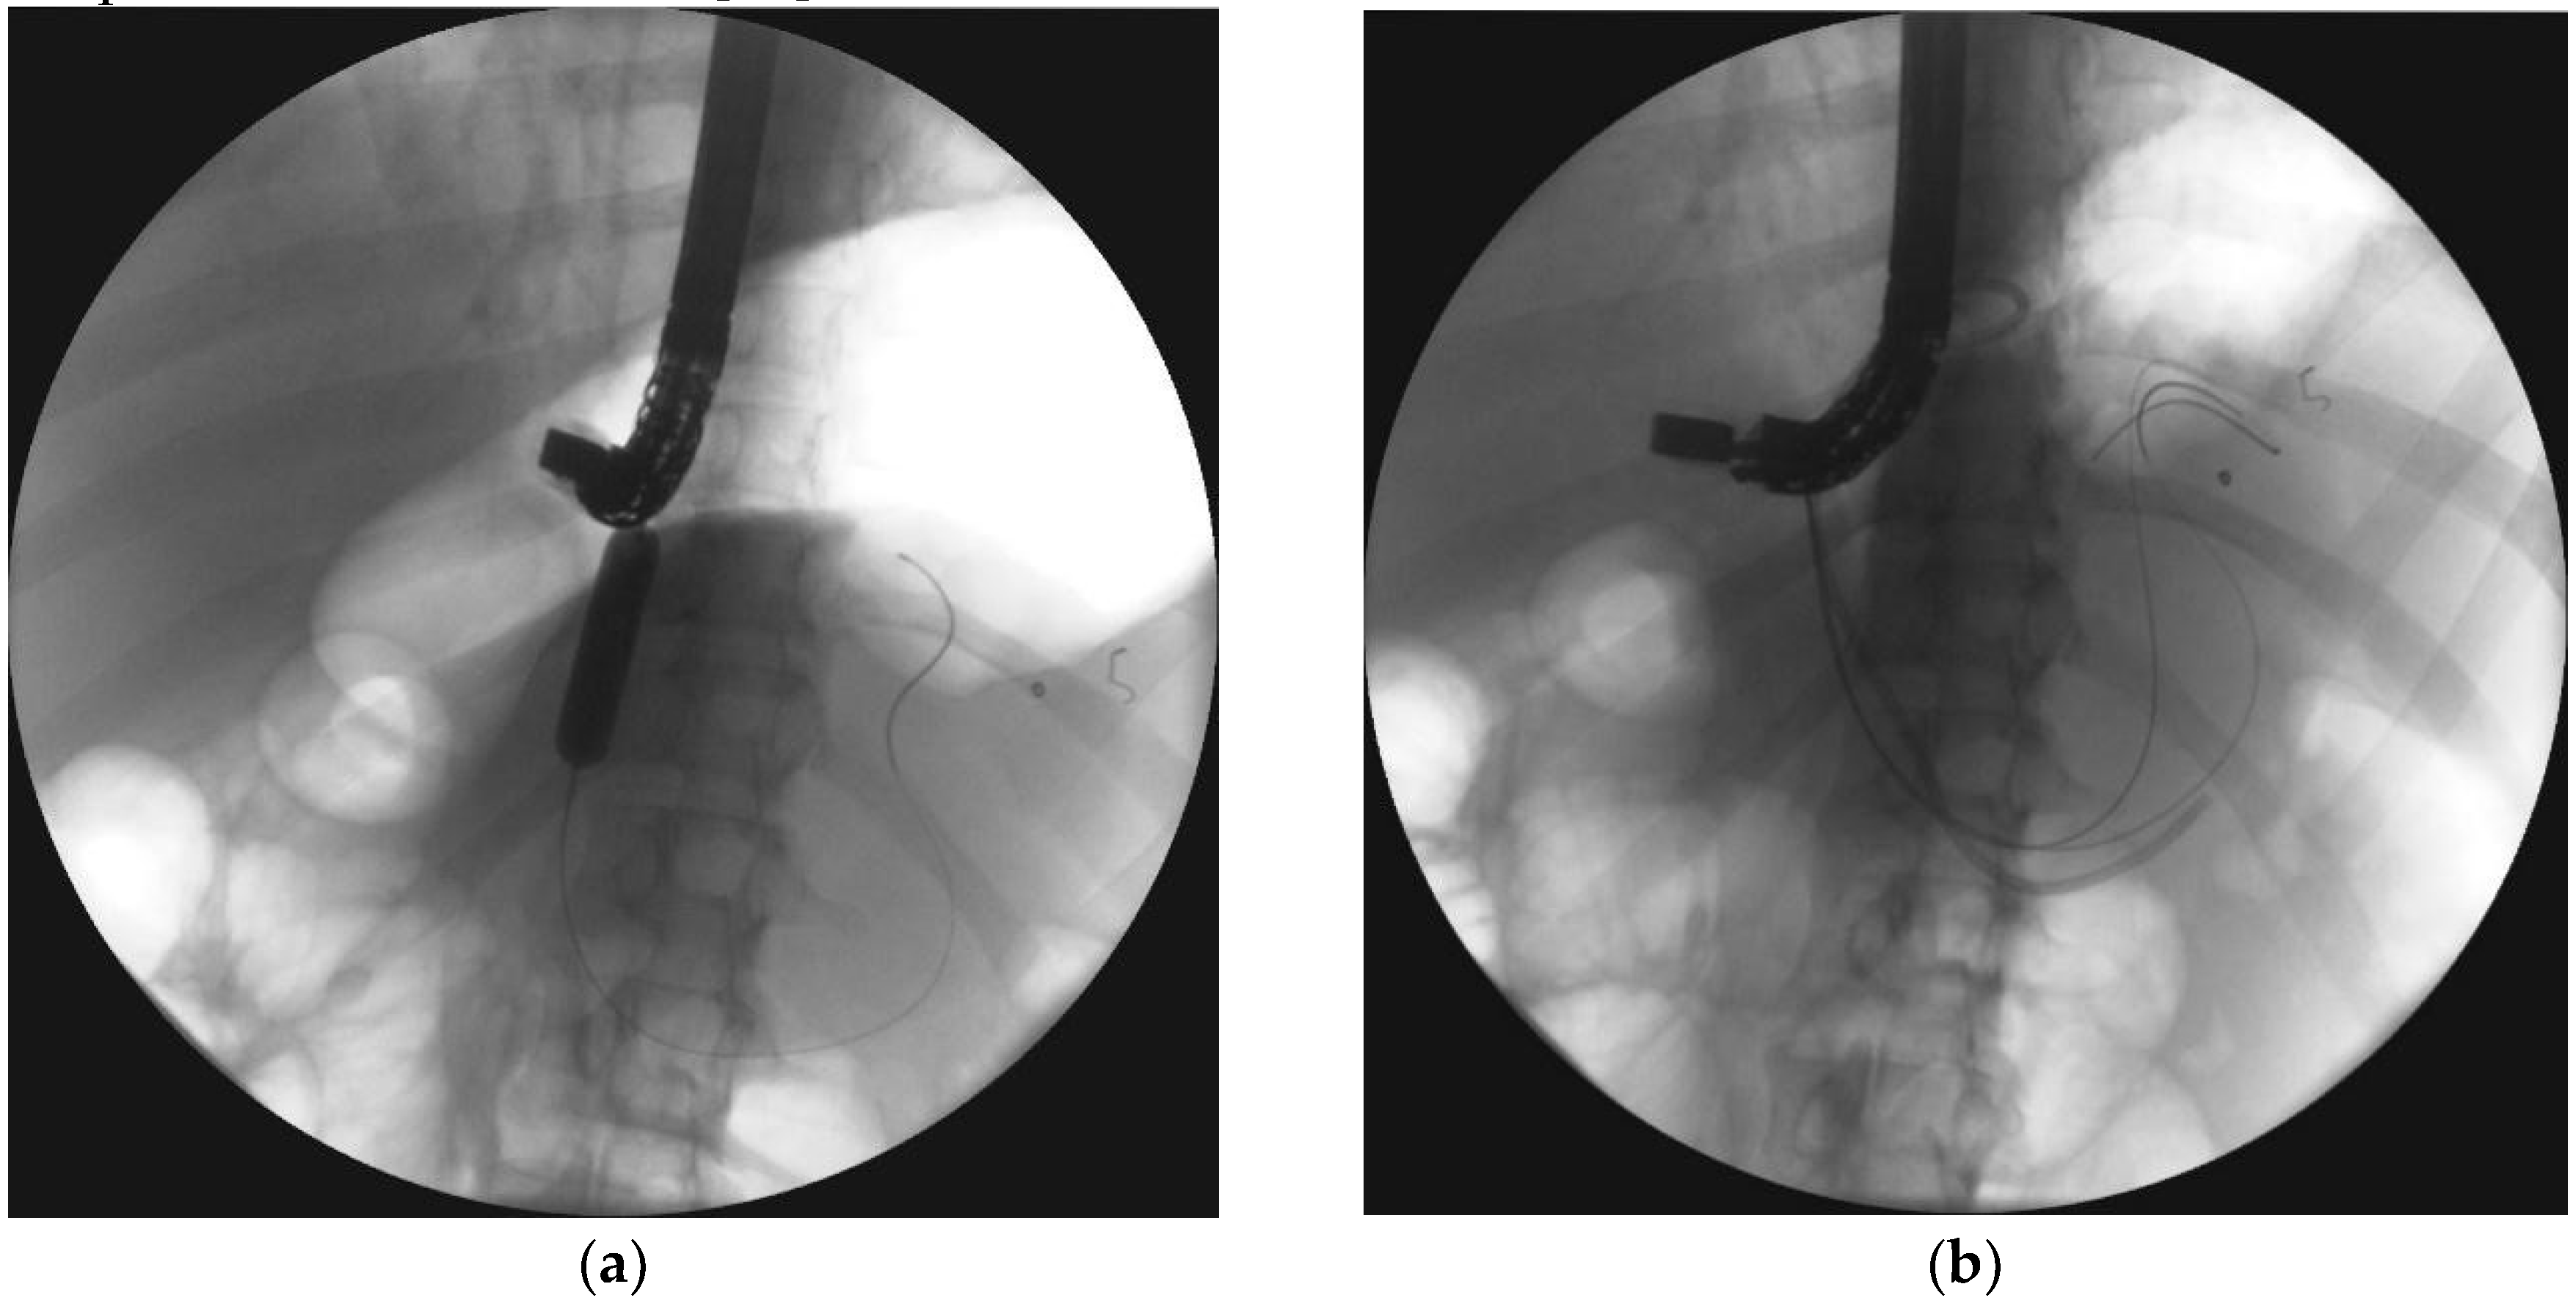

4. Transpapillary Endoscopic Drainage

- Smoczyński, M.; Jagielski, M.; Jabłońska, A.; Adrych, K. Endoscopic necrosectomy under fluoroscopic guidance- a single center experience. Wideochir. Inne. Tech. Maloinwazyjne. 2015, 10, 237–243. [Google Scholar] [CrossRef] [PubMed]

- Smoczyński, M.; Jagielski, M.; Siepsiak, M.; Adrych, K. Endoscopic necrosectomy through the major duodenal papilla under fluoroscopy imaging. Arch. Med. Sci. 2018, 14, 470–474. [Google Scholar] [CrossRef] [PubMed]